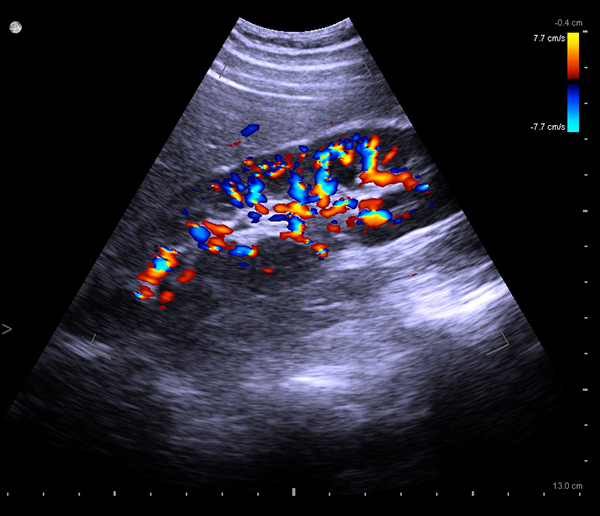

Ultrasound for Kidney

BK Medical systems provide high-resolution image quality for advanced kidney imaging, measurement, and biopsy. See anatomical details and variations and find kidney stones. Visualize and measure blood flow with highly sensitive color Doppler.